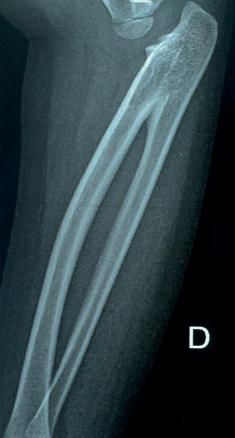

À la radiographie de l’avant-bras et du coude : fusion des parties proximales de radius et de l’ulna (fig. 1 et 2).